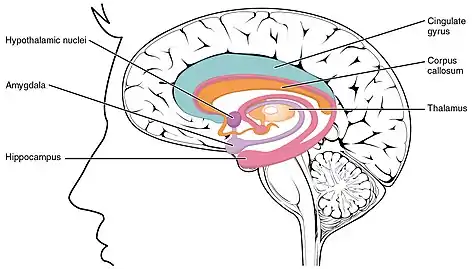

Location of important brain structures associated with LENAS. Note the thalamus and corpus callosum.

LENAS is seen with damage to the white matter and axons within the brain. The external human LENAS brain shows findings in several major structures. There is mild atrophy of the frontoparietal regions of the brain and a mild reduction of the thalamus and rostral (front) part of the caudate nucleus (which is located in an area of the brain called the basal ganglia).[4] Abnormalities in the frontal, frontoparietal, and temporal lobes are most severe and predominant with LENAS and asymmetry of the cerebral hemispheres has sometimes been found.[4] LENAS also may show moderately enlarged lateral ventricles and atrophy in corticospinal tracts as well as in the pons.[4]

The area where it is seen to be the most pronounced abnormalities appear in the white matter below the pre- and postcentral gyri that extend through the posterior limb of the internal capsule into pyramidal tracts of the brain stem.[4]

Specific Immunostains are used as the easiest identification of neuroaxonal spheroids in LENAS which appear as round to oval shaped swellings and are seen in affected white matter.[4] If there appears to be a large amount of loss in myelin sheaths on axons and these spheroids, LENAS progressed to become widespread.[4]